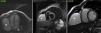

Magnetic resonance imaging (MRI) (Figure 4) identified a non-enhanced, well-defined bilobed mass in the right costophrenic angle containing clear fluid with a volume of 70.4 ml, compatible with a giant pericardial cyst.